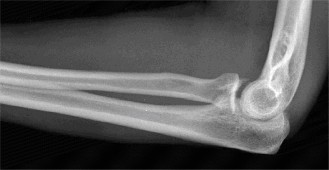

A 54-year-old male presented to the ED with left elbow pain after sustaining an injury in a low speed motor vehicle accident. He denied any other injuries. On examination, he had no open injuries and was neurovascularly intact. He had gross deformity about the elbow. His images are below (Figs. 2–89 to 2–92).

Figure 2–89 Pre- and post-reduction films showing complex elbow dislocation, coronoid fracture.

The correct answer is (C). Posteromedial complex elbow dislocation. This injury is proposed to result from axial load combined with posteromedial rotation, varus force, and elbow flexion. This is opposed to the more frequently seen posterolateral dislocation. There is a fracture of the coronoid, which is typical for this type of injury.